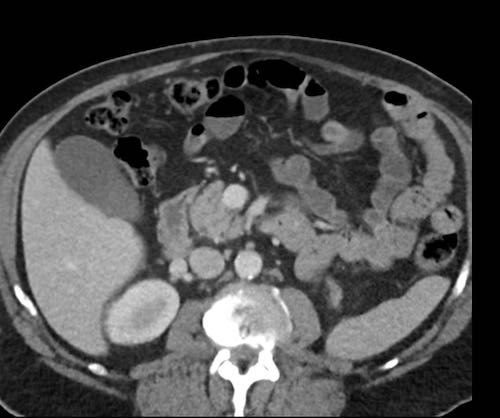

Ca lâm sàng 1

Cuộn qua các lát cắt.

Bạn có thể phát hiện tất cả các tổn thương cấy ghép phúc mạc không?

Bệnh nhân này đã được phẫu thuật và toàn bộ phúc mạc được ghi nhận phủ kín bởi các tổn thương u dạng kê.